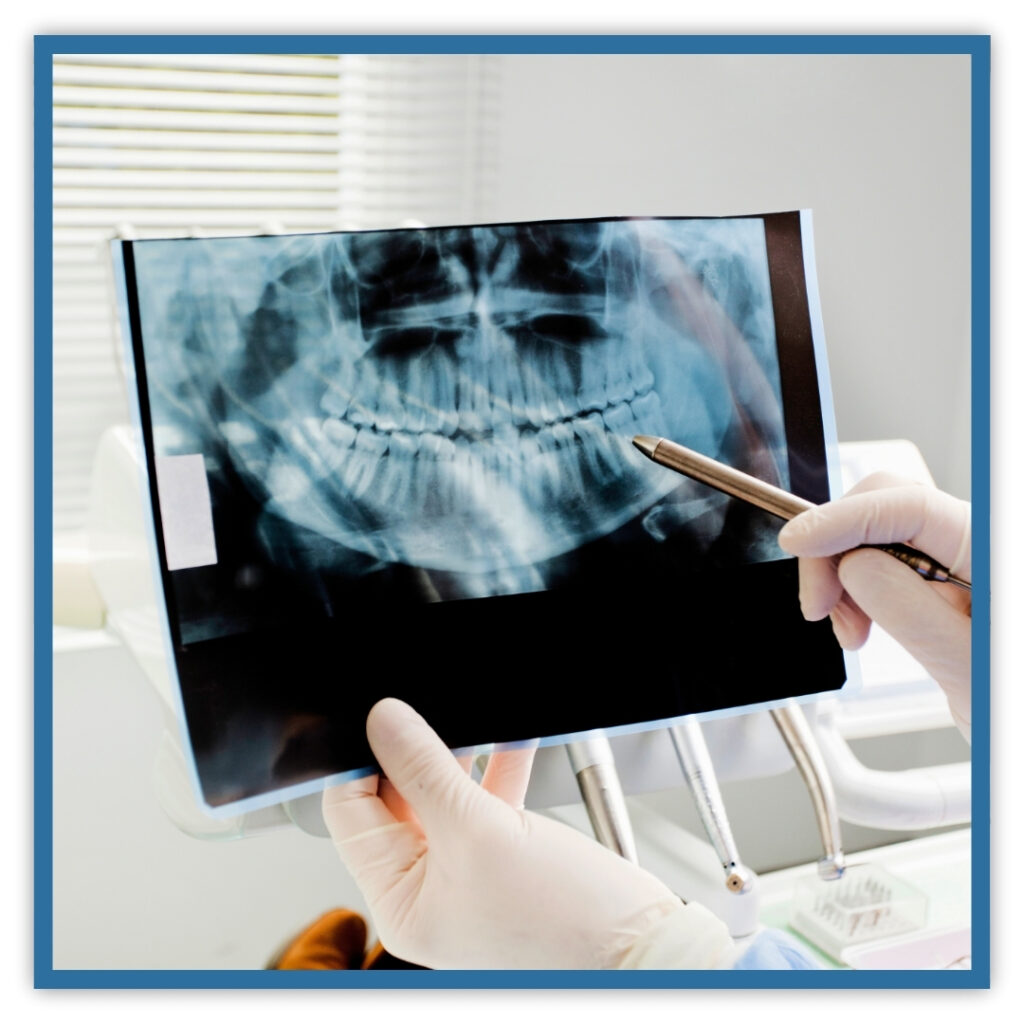

Before performing X-ray procedures, students must now complete a Board-approved 8-hour infection control course and maintain current, valid certification in Basic Life Support (BLS). Our training programs integrate this essential instruction, ensuring students develop critical skills necessary for patient safety and compliance in today’s dental practices.